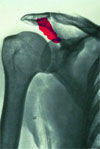

Kaletka maziowa podbarkowa (bursa subacromialis) w stanie chronicznego zapalenia.

Kaletka podbarkowa w nagłym stanie zapalnym.